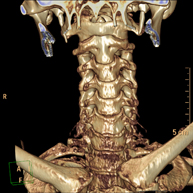

- TC Columna cervical Prueba radiológica que consiste en obtener imágenes de las vertebras cervicales de alta definición anatómica mediante el empleo de un equipo de TC (Tomografía Computarizada). Indicaciones: cervicalgia sin/con irradiación a brazos, traumatismo. Prueba radiológica que consiste en obtener imágenes de las vertebras cervicales de alta definición anatómica mediante el empleo de un equipo de TC (Tomografía Computarizada). Indicaciones: cervicalgia sin/con irradiación a brazos, traumatismo.

- Columna- TC Columna cervical Prova radiològica que consisteix en obtenir imatges de les vèrtebres cervicals d'alta definició anatòmica, mitjançant l'ús d'un equip de TC (Tomografia Computeritzada). Indicacions: dolor cervical amb/sense irradiació als braços, traumatisme, malformacions congènites. Prova radiològica que consisteix en obtenir imatges de les vèrtebres cervicals d'alta definició anatòmica, mitjançant l'ús d'un equip de TC (Tomografia Computeritzada). Indicacions: dolor cervical amb/sense irradiació als braços, traumatisme, malformacions congènites.